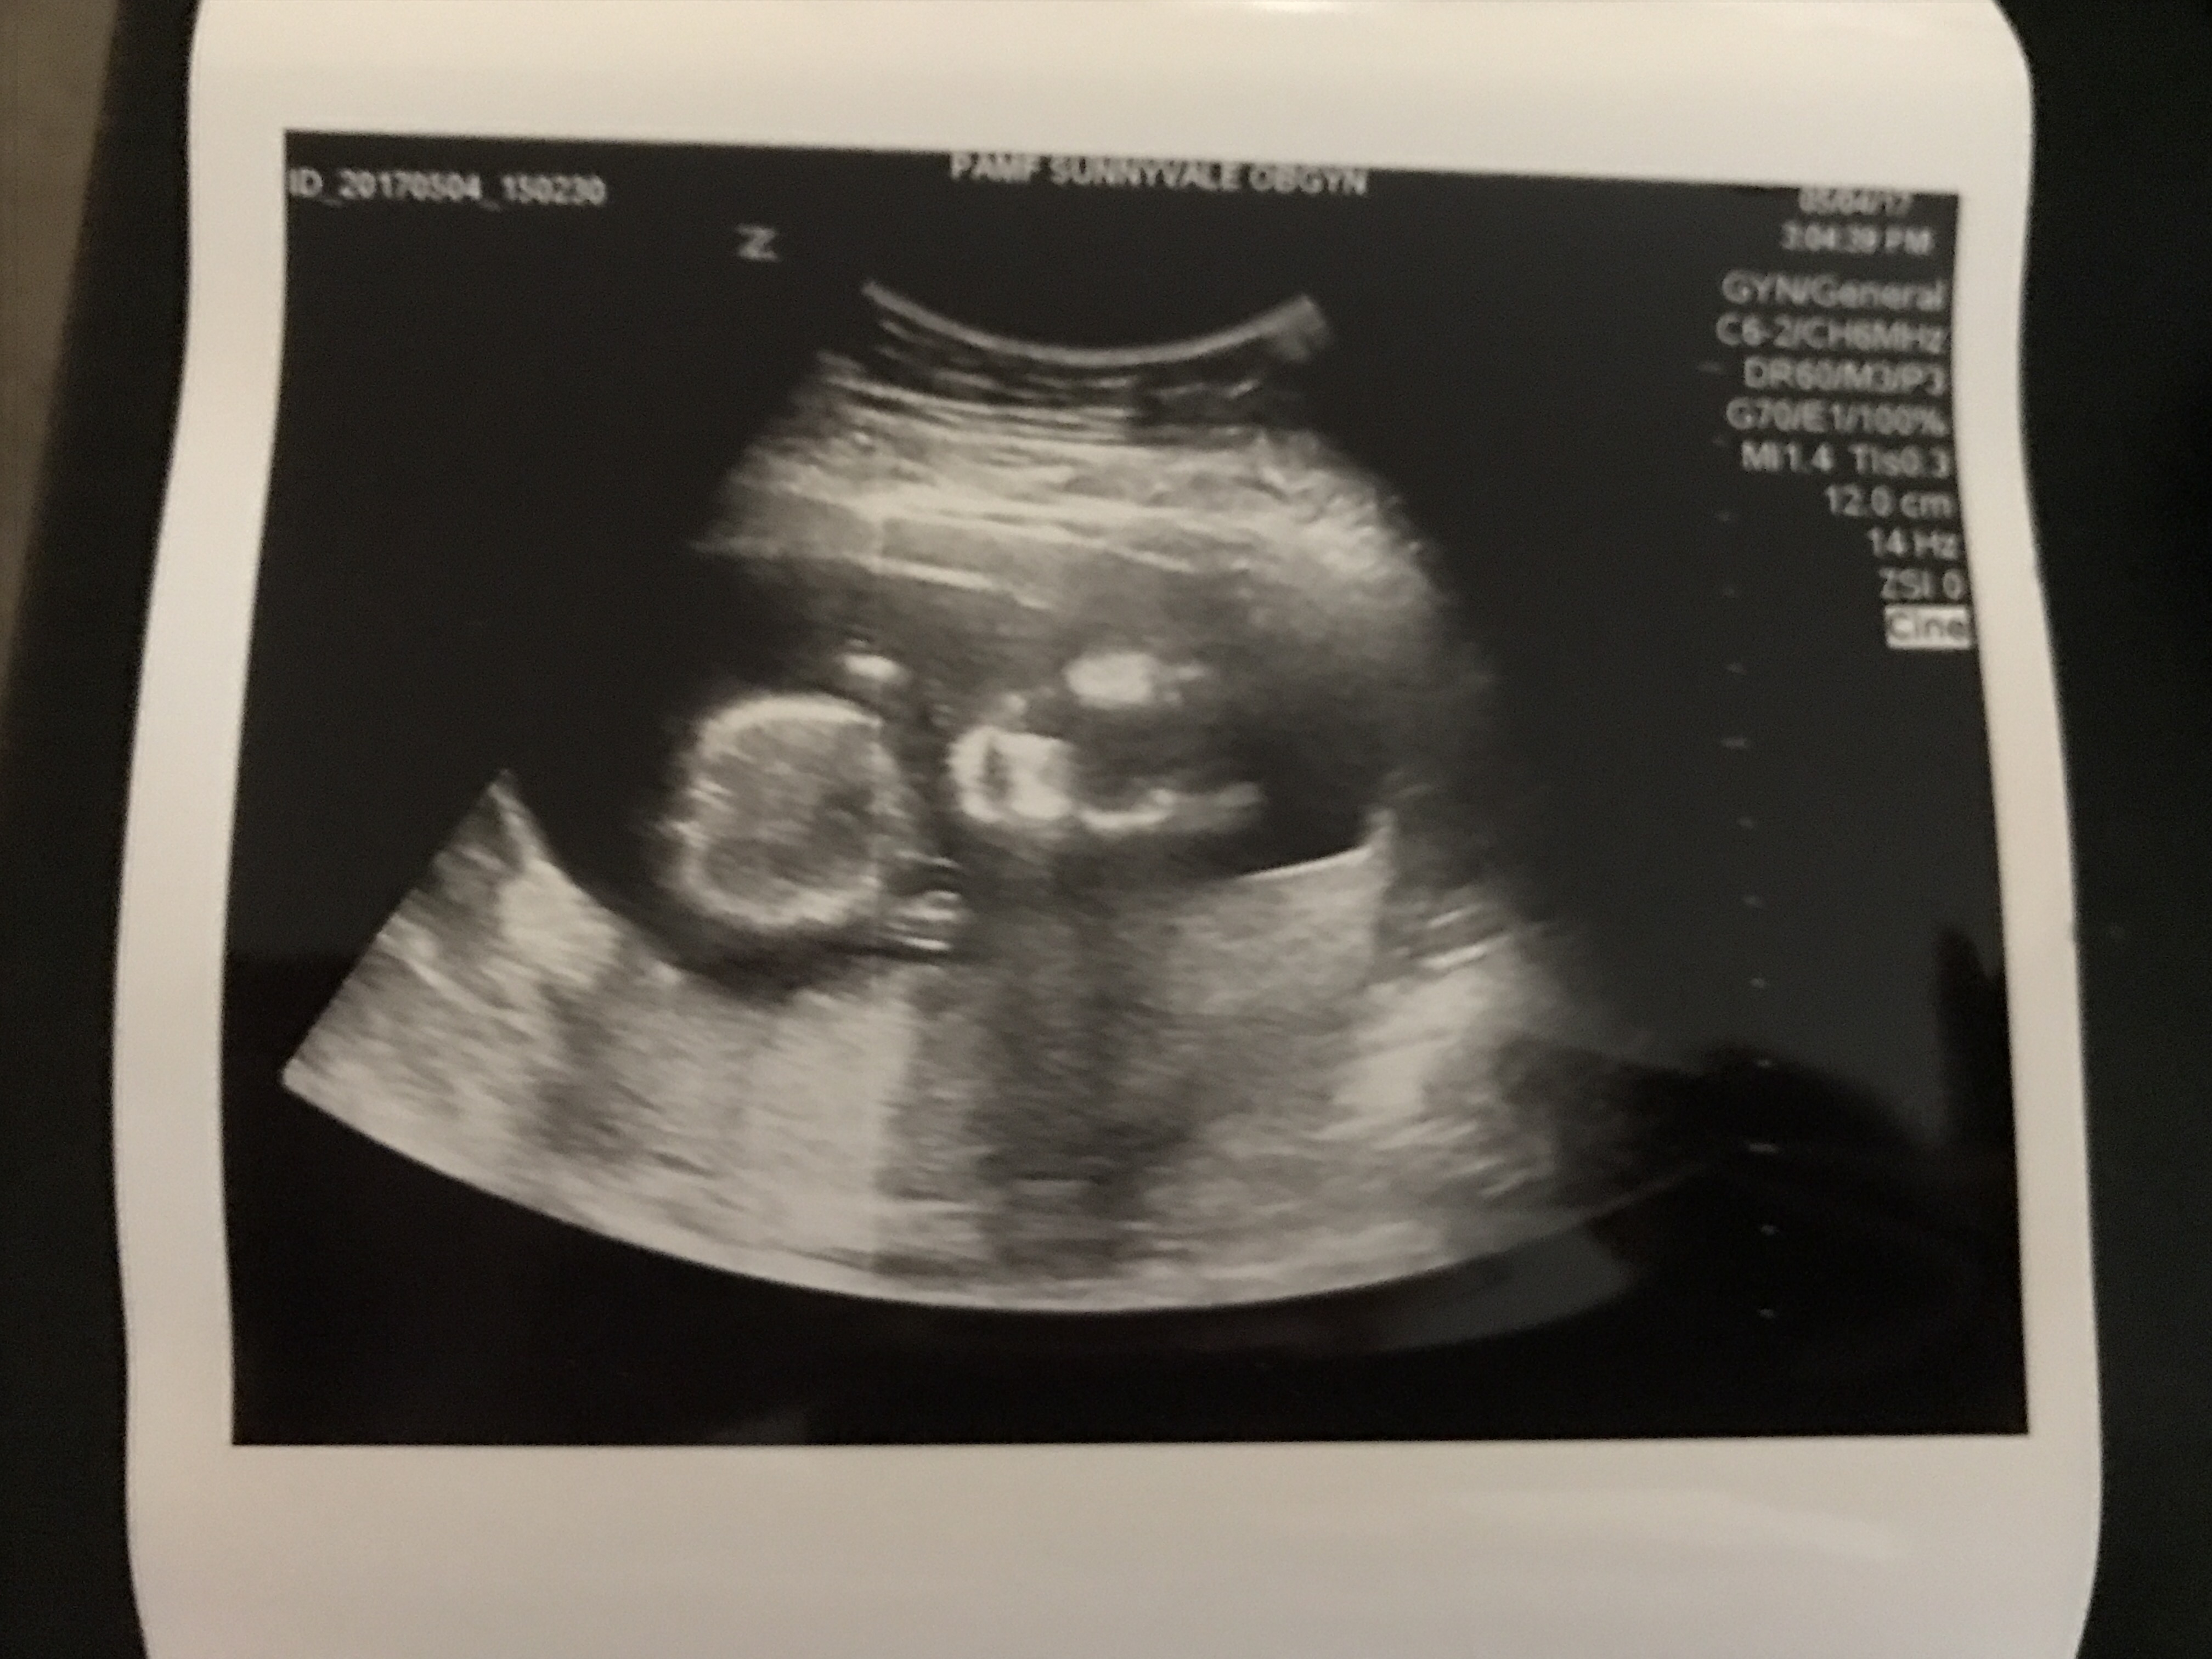

As usual getting an ultrasound was one of the highlights of our visit. I made sure to ask Dr. G if I would be able to tell the gender from these and had a sleep mask I was prepared to wear so as to not see inadvertently if that was the case, but he assured me these would not give it away, so I was able to look and take some photos home with me. At one point baby made a fist for us, I’m not sure if it is in one of these photos, but if it is my guess is it is in this one below.

Dr. G. pointed out some of baby’s features to us that he had not before including his or her spine. I remarked that it look good to me, and he agreed that it looked good to him also. It’s so amazing to get to see these great peeks at our developing baby, even if it’s hard to figure out what a lot of the photos are, in fact I have a few from him that I can’t make out much of anything from in addition to the great detailed ones I’m posting.